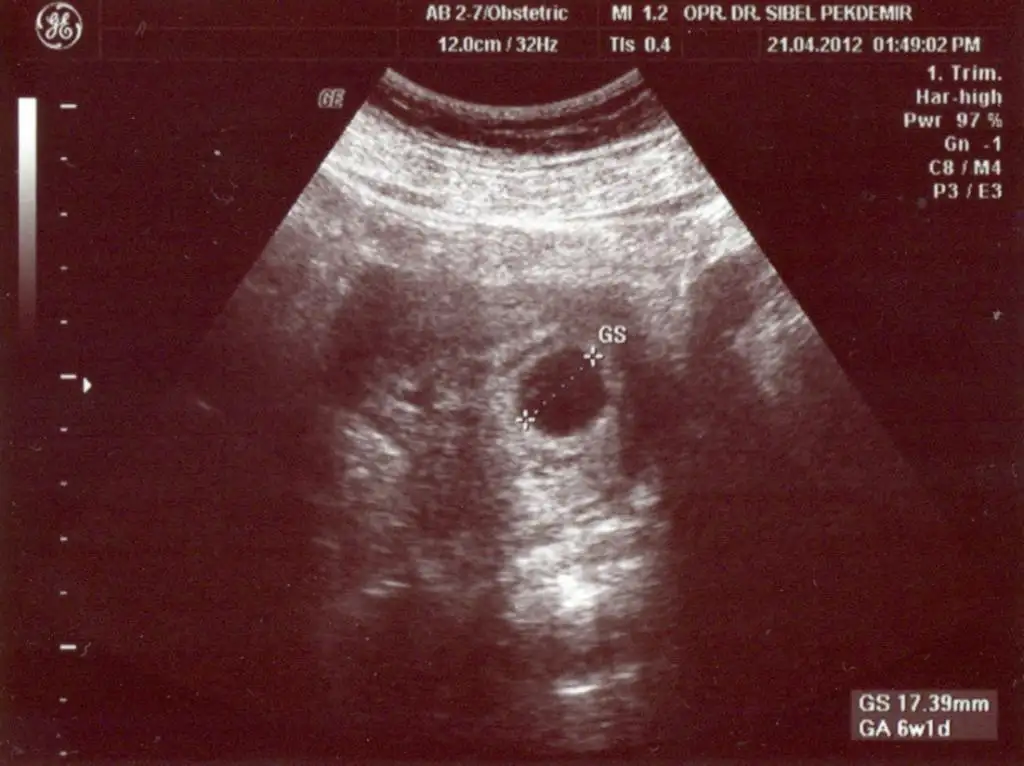

selam kızlar benim keseyi de ekledim :) geçen ctesi çekildi. umarım ekleyebilmişmdir bu arada: )

Eki Görüntüle 400583